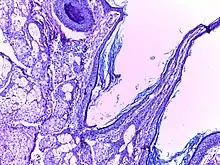

![]() | Benign cystic teratoma | Micrograph of Teratoma Ovary showing areas of cartilage, mucous glands, squamous epithelium and hair follicle. | Category: Histopathology of mature teratoma of ovary | teratoma |